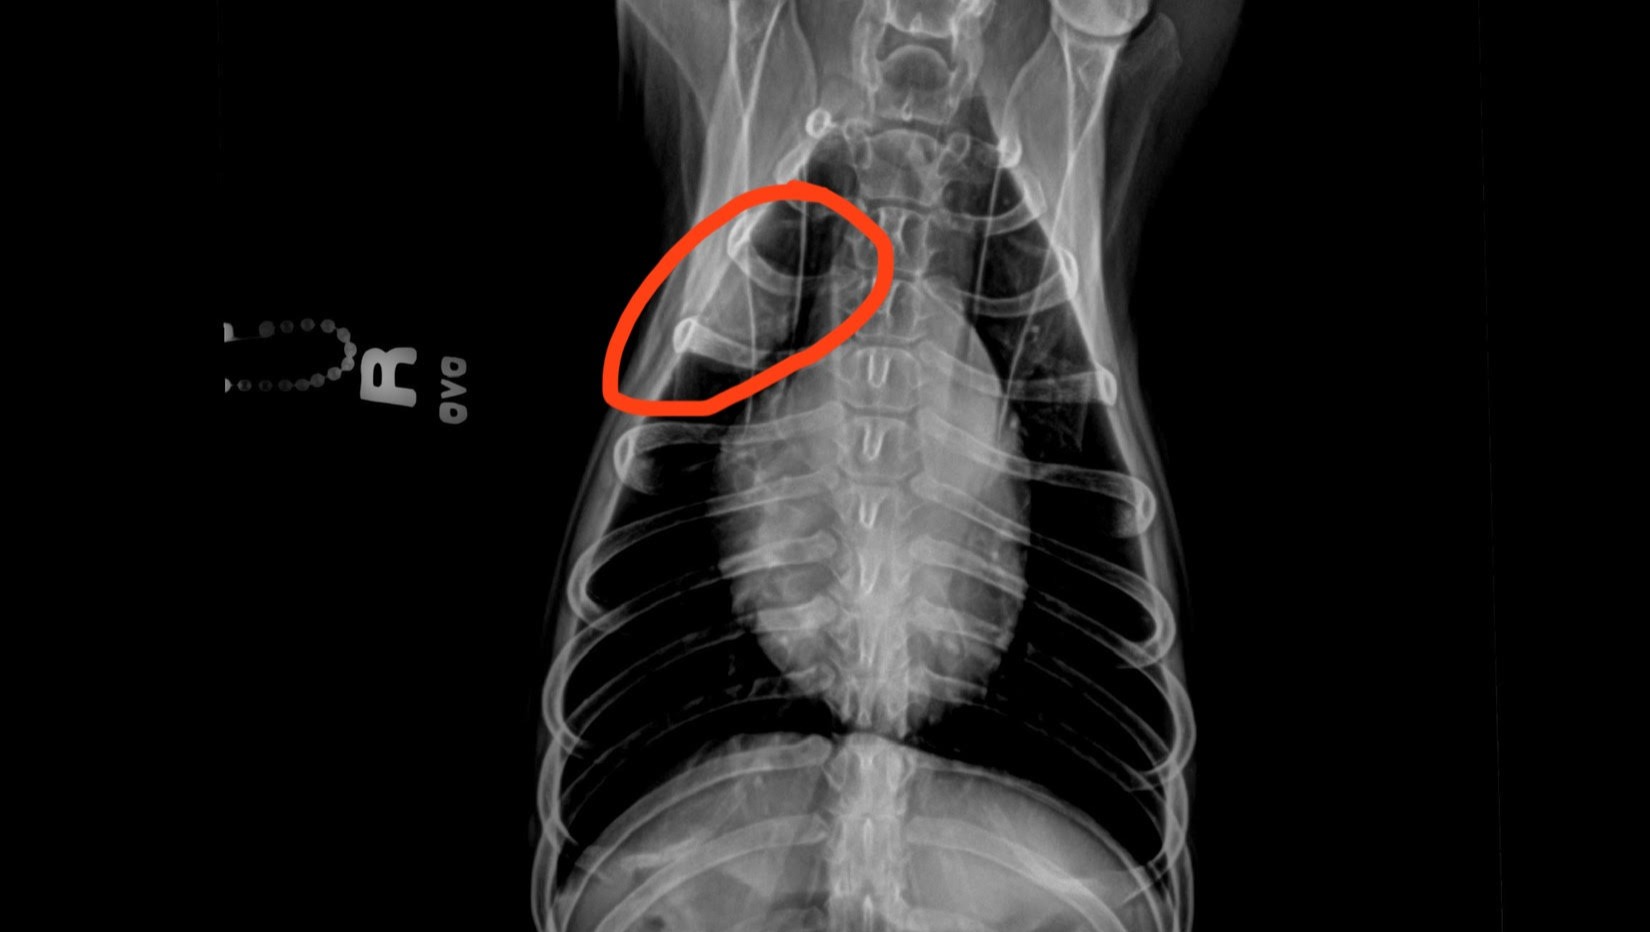

On November 11, 2024, Koa was brought into the clinic for a routine dental under anesthesia. Part of his senior screening included taking x-rays of his chest and abdomen. This is where we first saw the mass in his lungs. His dental was canceled and we performed an abdominal ultrasound which also found a small mass on his liver, and we were suspicious of the findings on his spleen. We were referred to a specialist for a CT scan to determine the next best steps. Our initial worry was that this was a cancer that had spread and made its way from the lungs to the liver and beyond.

However, the scan found that they are two separate masses (which is a better scenario, although, not ideal). The scan also found potential evidence that the mass from the right lung lobe had spread to his left lung lobe, but it could not definitively be determined.

Attached, you will find images of the lung mass from the x-rays circled in red. You will also find the image from the abdominal ultrasound confirming the presence of the mass on his liver marked by green lines indicating approximate measurements.